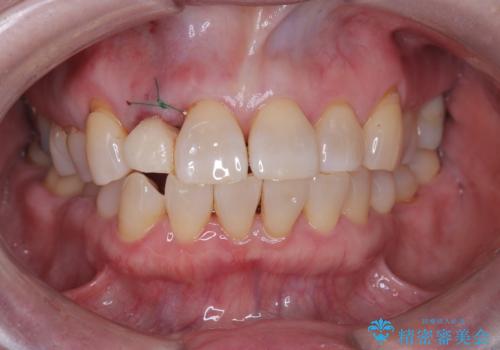

そのため今回は、右上2番を抜歯し、右上1番および左上1番をオールセラミッククラウンで審美的に修復しました。

また、歯科治療への不安が強かったため、静脈内鎮静法を併用してリラックスした状態で治療を行いました。